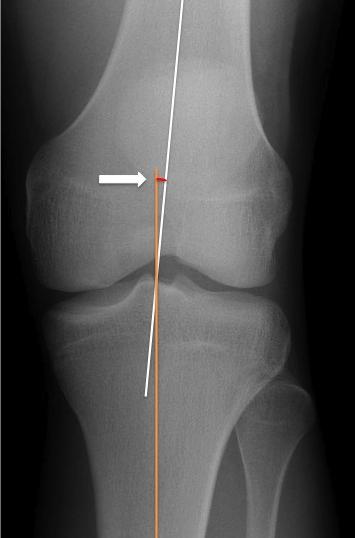

Using the AP view of the knee, angle formed between femur axis and tibia axis. Tibiofemoral angle positive if both axes have external concavity; negative if both axes have internal concavity.

if < 0 degrees then varus deformity ( RID4769 )

if > 10 degrees then valgus deformity ( RID4768 )

how to draw the tibiofemoral angle